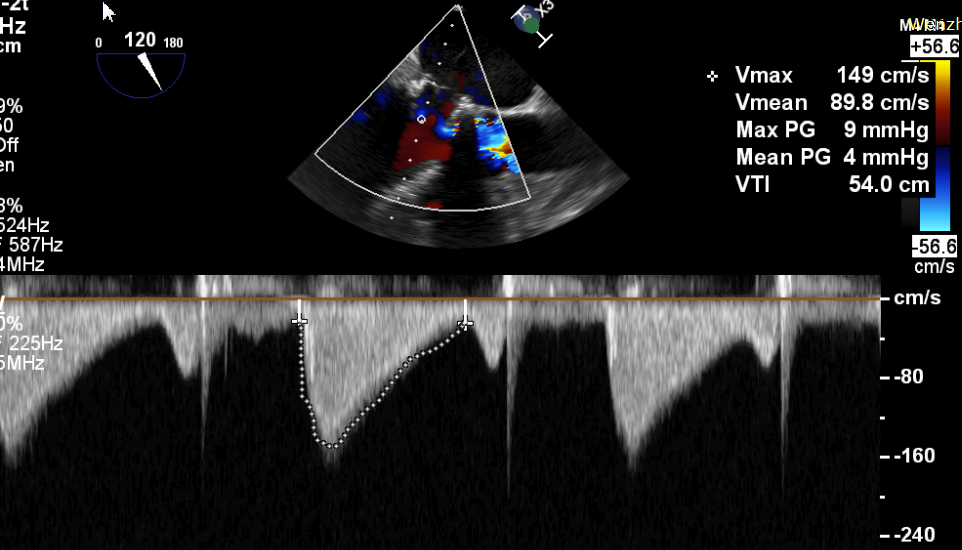

患者,男,70岁,于1月前无明显诱因下出现活动后胸闷,步行100米后出现气促伴双下肢乏力,无胸痛、发热、头晕头痛、发热畏寒、恶心呕吐及咳嗽等不适。患者于7年前行二尖瓣生物瓣置换术(Edwards Perimount 27#)。术前心脏超声提示:二尖瓣生物瓣置换术后:生物瓣重度狭窄(有效瓣口面积0.58cm²,MPG=12mmHg);左房增大(57mm)左室增大(舒张末前后径73mm),左室壁静息状态下运动弥漫性减弱,左室收缩功能明显减低(EF=29%,Simpson法);轻度肺动脉高压;术前心功能IV级。

CDFI提示过瓣血流通畅

CDFI示少量瓣周漏

收缩期未见瓣周漏